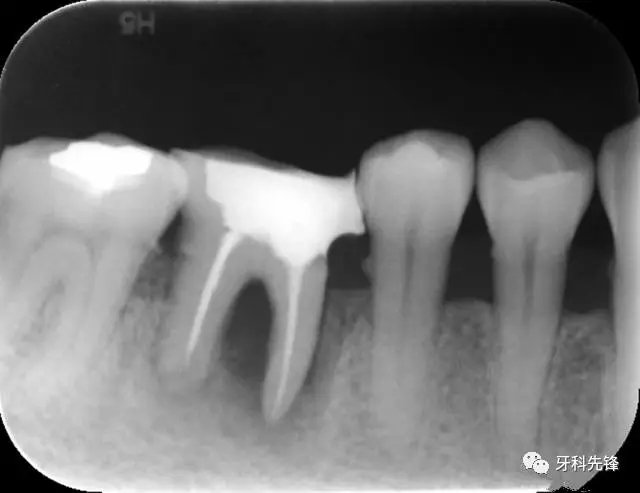

圖1 術前X光片

640.webp.jpg

X 示:15  根管透射,根尖有陰影

14  根管阻射,恰填,無異常

46  根管阻射,恰填,根分叉骨密度降低,近中根尖陰影較大